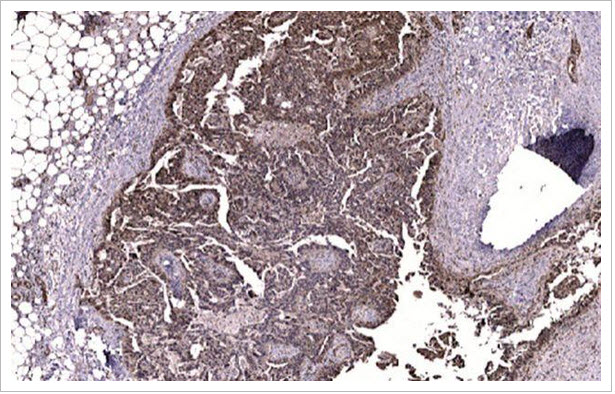

Caption Staining of a tumor biopsy isolated from a patient with ovarian cancer shows elevated levels of activated FAK (brown) within a tumor implant compared to surrounding normal tissue. Credit : UC San Diego Health Sciences

In the majority of patients, ovarian tumors exhibit high levels of FAK, said Dwayne G. Stupack, PhD, associate professor in the Division of Gynecologic Oncology at Moores Cancer Center and co-principal investigator.